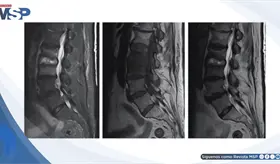

Un dolor de cabeza que empeora al estar de pie y mejora al acostarse es una señal de alerta. Esta cefalea ortostática fue la clave para identificar que no se trataba de migraña, sinusitis ni cambios hormonales, sino de un problema con la presión del líquido que rodea el cerebro.

La enfermedad avanzó de forma silenciosa durante años, manifestándose únicamente con cambios de personalidad, deterioro cognitivo e incontinencia, lo que llevó a un diagnóstico tardío.